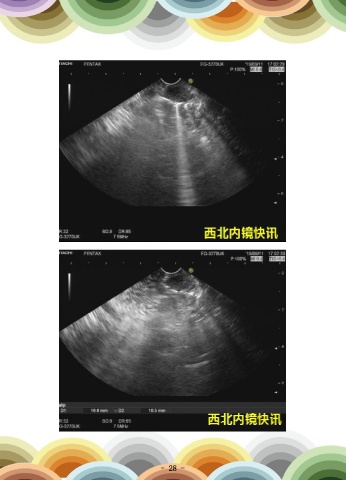

一例急性化脓性胆管炎急诊ERCP取石及胆管引流治疗

资料提供:赵刚 交大二附院消化内科

患者女性,56岁,以“间断腹痛1周,加重伴寒战高热1天”之主诉入院。患者1周

前进食油腻食物后出现右上腹痛,为阵发性绞痛,向右侧肩背部放射,同时伴有恶心及

呕吐,所吐为胃内容物,自行服用奥美拉唑、阿莫西林等药物后症状无明显改善,后于

当地县医院住院治疗,查肝功提示胆红素及转氨酶显著升高,行上腹部CT及MRCP检查

提示胆总管下端结石并低位胆道梗阻可能,患者在当地住院期间腹痛加重,同时开始寒

战及高热,体温最高39.5℃,遂急诊转入我院。因考虑患者“胆总管结石并急性胆管炎”

临床诊断成立,遂于入院当日上午安排行急诊ERCP术,术中顺利进行胆管插管,抽出白

色脓性胆汁约10ml送检细菌培养,胆道造影可见肝总管处柱状充盈缺损影,顺次进行十

二指肠乳头括约肌切开(EST)及十二指肠乳头球囊扩张术(EPBD),之后顺利自胆管

内取出块状结石数枚,并冲洗出大量脓性胆汁,留置鼻胆引流管后结束手术,用时约35

分钟。患者术后当日体温降至正常,术后第二天开始进食,术后第五天复查血常规恢复

正常,肝功提示转氨酶(术前ALT 479 IU/L,AST 229IU/L;术后ALT 83 IU/L,AST

40IU/L)及胆红素(术 前 TBIL 188.68 μmol/L,DBIL 110.61μmol/L;术后TBIL

31.39μmol/L,DBIL 12.39μmol/L)均较术前显著改善,后患者顺利康复出院。

胆管插管 胆管造影可见充盈缺损